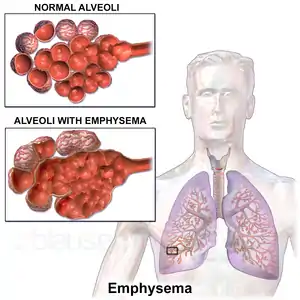

Emphysema is any air-filled enlargement in the body's tissues.[6] Most commonly emphysema refers to the enlargement of air spaces (alveoli) in the lungs,[6] and is also known as pulmonary emphysema.

Emphysema is a lower respiratory tract disease,[7] characterised by enlarged air-filled spaces in the lungs, that can vary in size and may be very large. The spaces are caused by the breakdown of the walls of the alveoli, which replace the spongy lung tissue. This reduces the total alveolar surface available for gas exchange leading to a reduction in oxygen supply for the blood.[8] Emphysema usually affects the middle aged or older population because it takes time to develop with the effects of tobacco smoking,[2] and other risk factors. Alpha-1 antitrypsin deficiency is a genetic risk factor that may lead to the condition presenting earlier.[9]

There are four types of emphysema, three of which are related to the anatomy of the lobules of the lung – centrilobular or centriacinar, panlobular or panacinar, and paraseptal or distal acinar emphysema – and are not associated with fibrosis (scarring).[17] The fourth type is known as paracicatricial emphysema or irregular emphysema that involves the acinus irregularly and is associated with fibrosis.[17] Though the different types can be seen on imaging they are not well-defined clinically.[18] There are also a number of associated conditions including bullous emphysema, focal emphysema, and Ritalin lung. Only the first two types of emphysema – centrilobular and panlobular – are associated with significant airflow obstruction, with that of centrilobular emphysema around 20 times more common than panlobular. Centrilobular emphysema is the only type associated with smoking.[17]